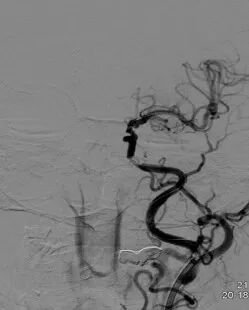

◆ 右侧颈内动脉以及右侧大脑中、前动脉显影良好,对左侧大脑中动脉部分代偿供血。

导丝怎么扩重磅!NOVA颅内药物球扩支架湖北首例植入!_https://www.jmylbn.com_新闻资讯_第6张

右侧颈内动脉造影